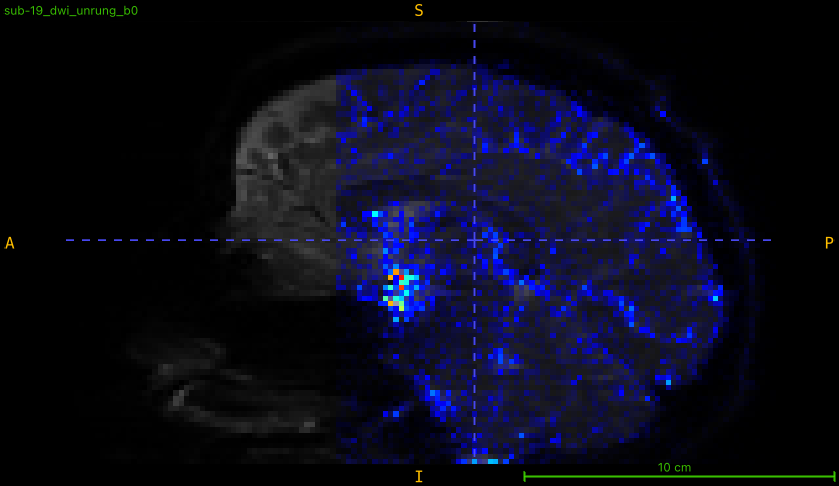

So I thought maybe it might have something to do with running dwidenoise first—went and tested out RPG on a couple raw scans (no reorenting to LPS or MP-PCA, just run locally on my machine via the TORTOISE Docker container), and much to my surprise…

It switched! Now the cutoff is a bit more rostral along the PE axis and it’s just the posterior portion of the brain that seems to have estimated/removed Gibbs artifacts. Here’s an example from a cs-DSI collected in May of this year (absolute value overlaid after subtracting the first raw and unrung b=0 volume):